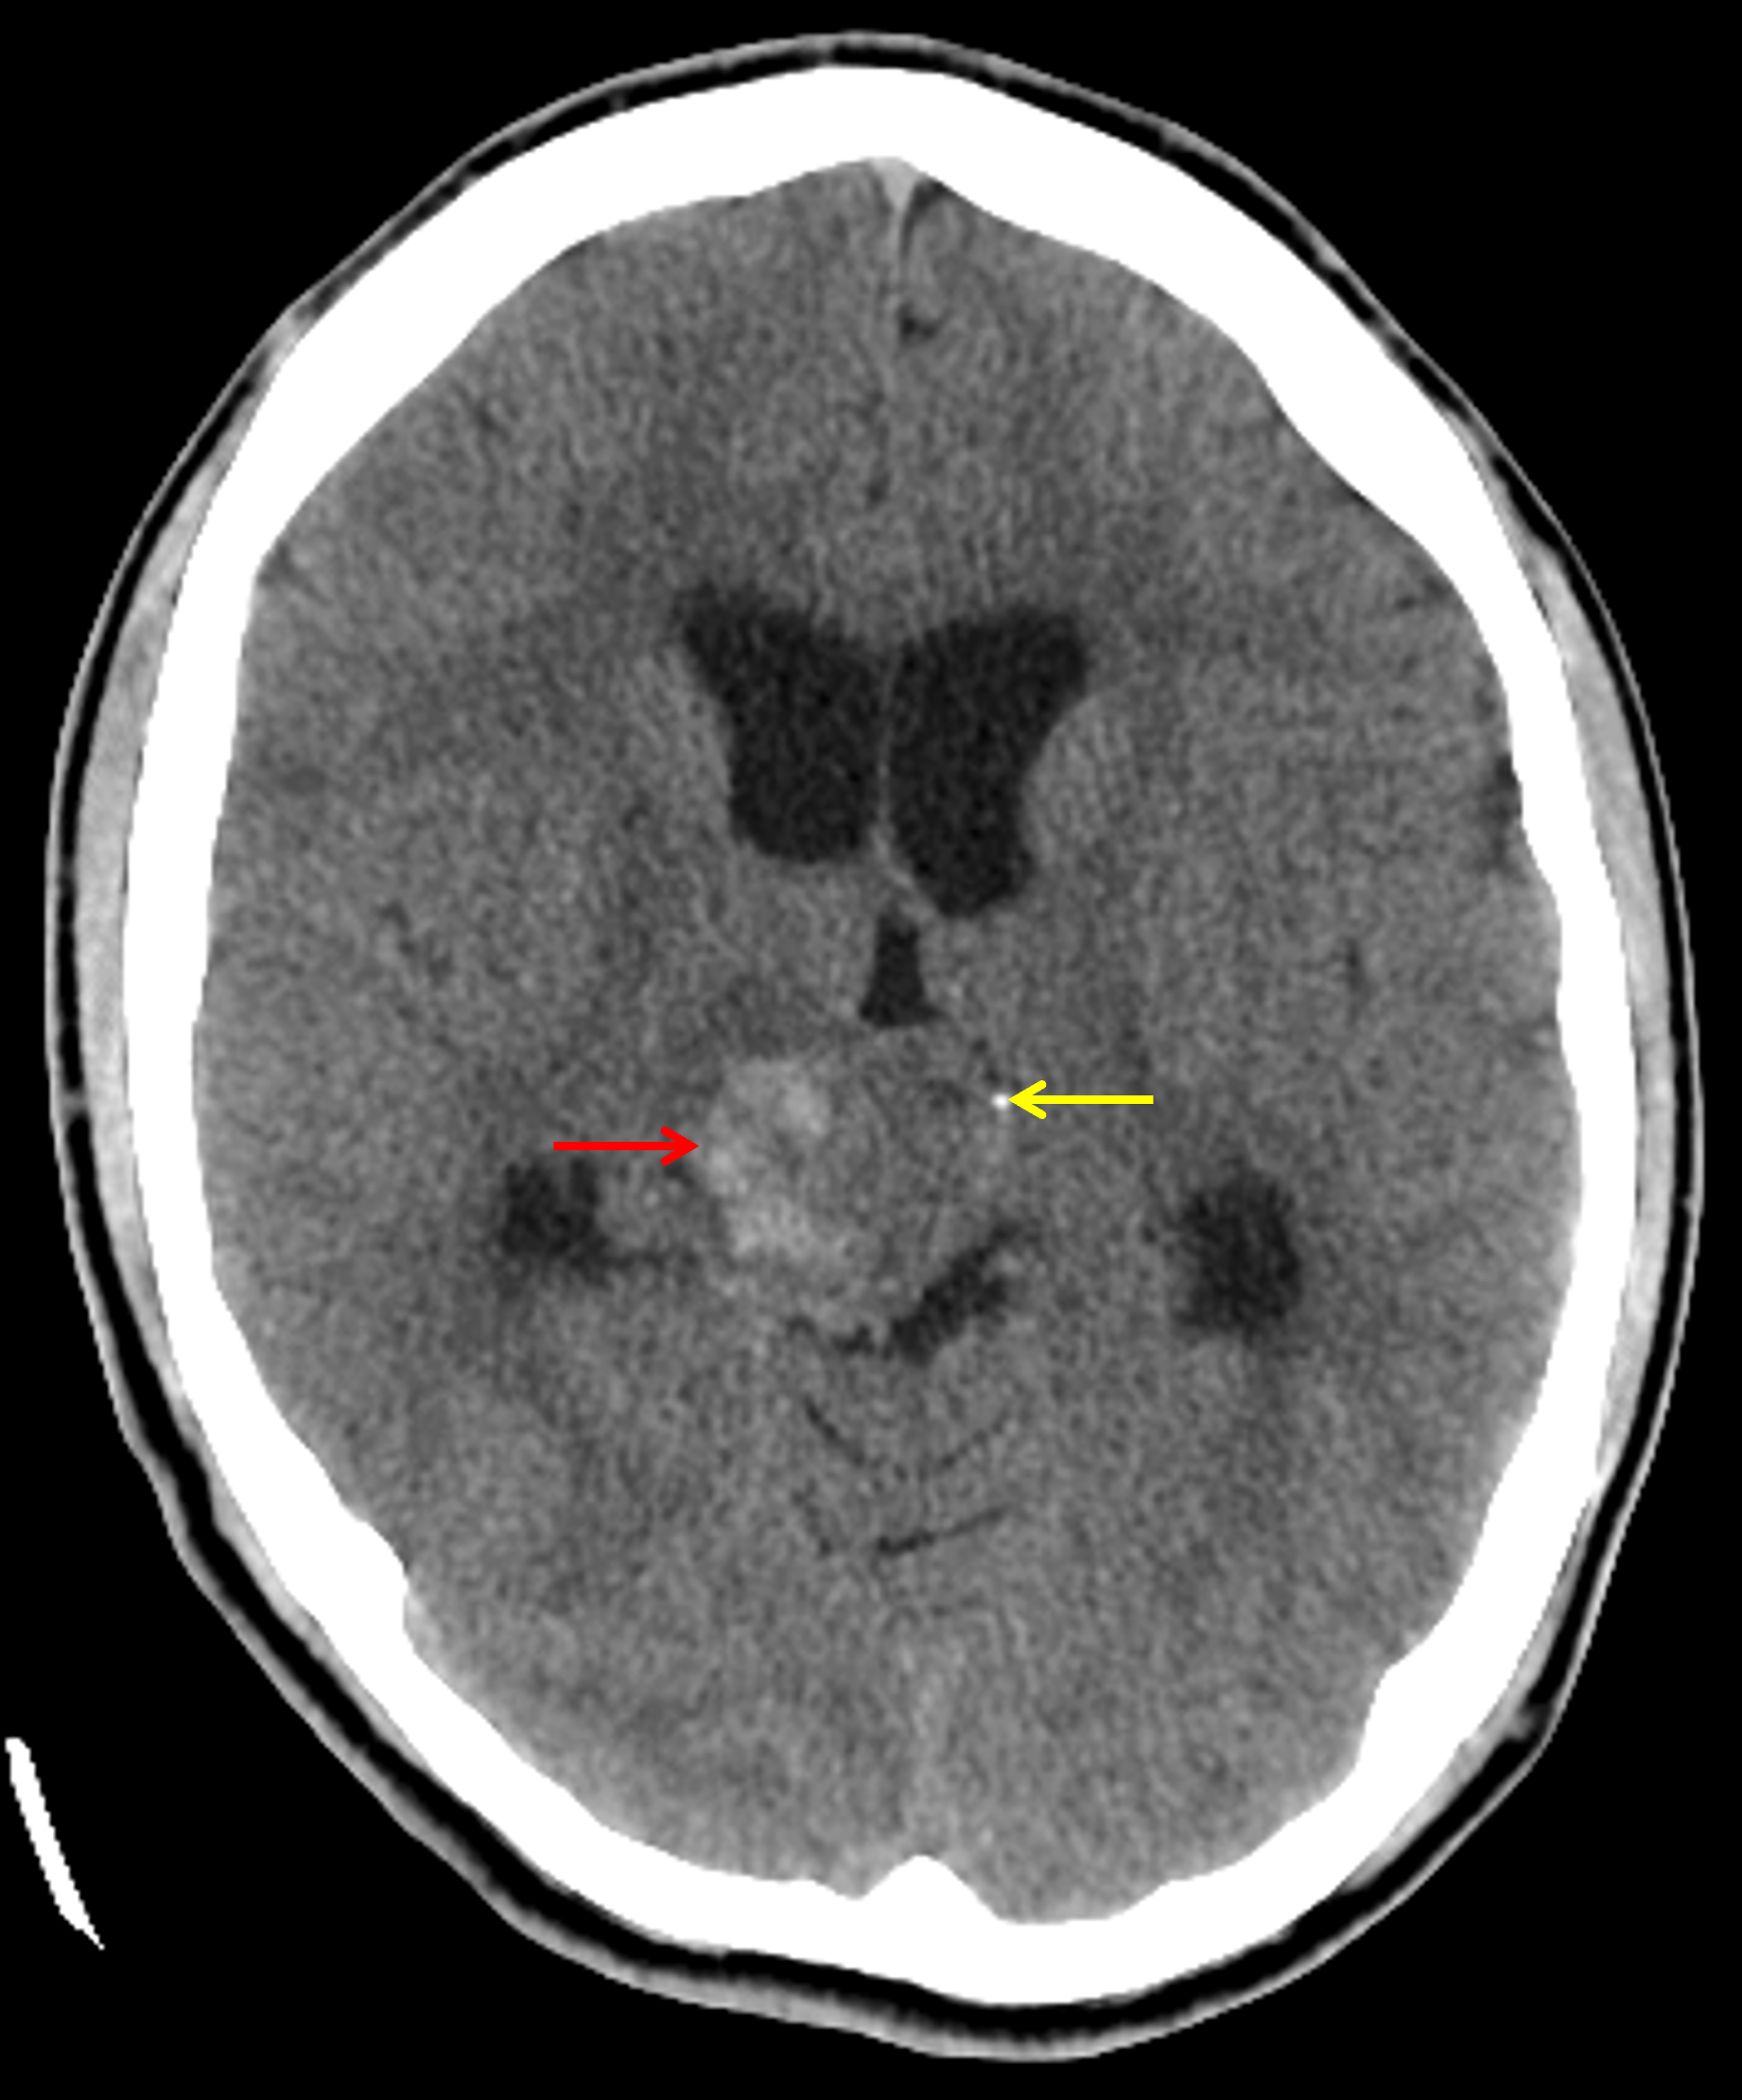

Age: 17

Sex: Male

Indication: Diplopia

CT

Teratoma (pineal region)